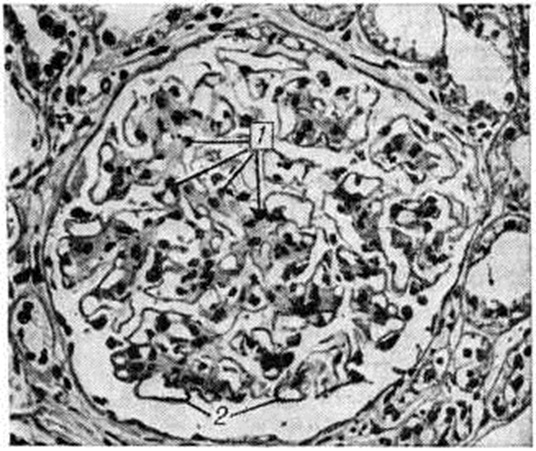

Смешанная форма характеризуется сочетанием типичных узелков с диффузным уплотнением мезангия и утолщением базальных мембран капилляров клубочков (рисунок 3). По данным электронно-микроскопических исследований утолщение базальных мембран капилляров клубочков возникает рано, нередко до появления каких-либо клинических проявлений поражения почек, и имеет место, видимо, при всех формах Гломерулосклероз диабетический Утолщение мембран наблюдается не только у больных, но и у молодых людей из диабетически отягощённых семей.

Рис. 3.

Электронограмма почки при смешанной форме диабетического гломерулосклероза (ранняя фаза): 1 — утолщение базальной мембраны, 2 — уплотнение мезангиального матрикса (базально-мембраноподобный материал); ×12 000.